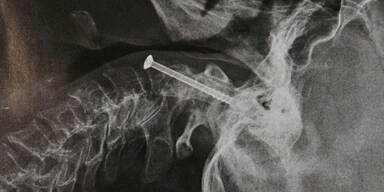

Die Steirerin wurde mit dem Hubschrauber ins LKH Graz geflogen und dort noch am gleichen Tag operiert. In der zweistündigen OP schoben die Ärzte den gebrochenen Halswirbel wieder an die richtige Stelle und fixierten ihn mit einer vier Zentimeter langen Schraube. Bereits am darauffolgenden Tag begann die 64-Jährige mit ihren "Therapie-Tauchgängen" in einer Druckkammer.